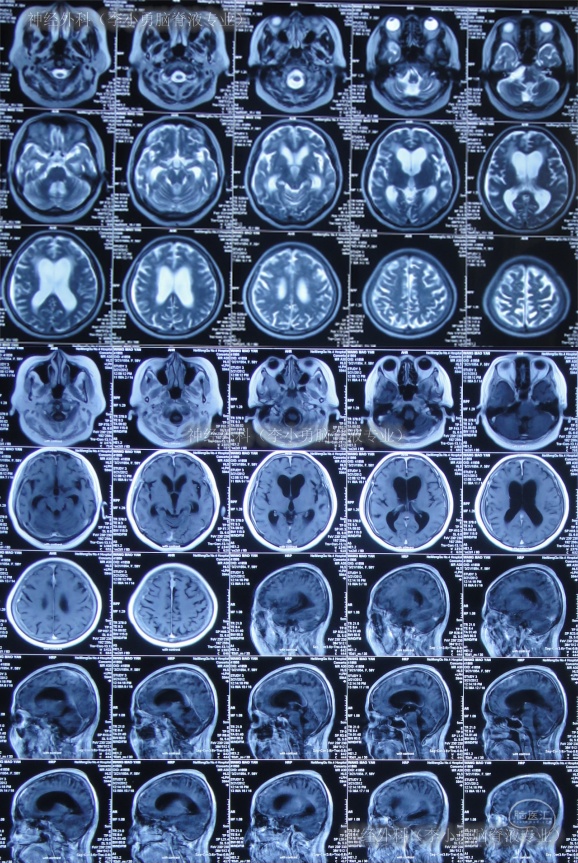

又过2月后即2011年10月14日,夜里2点起夜时突然站不稳,再次出现头昏,呕吐频繁,四肢无力,2011年10月17日第2次就诊于第2家医院:呼和浩特市某医院神经内科住院治疗,行头颅MRI(图-1)认为“末梢神经脱髓鞘病变,考虑为格林巴利综合征,轻度脑积水”。

图-1:2011年11月17日头颅核磁